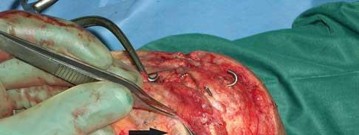

Video 27 shows the medial patellofemoral ligament running from the medial epicondyle of the femur to the medial portion of the patella. The posterior oblique ligament and the superficial medial collateral ligament run from medial epicondyle to the tibia.